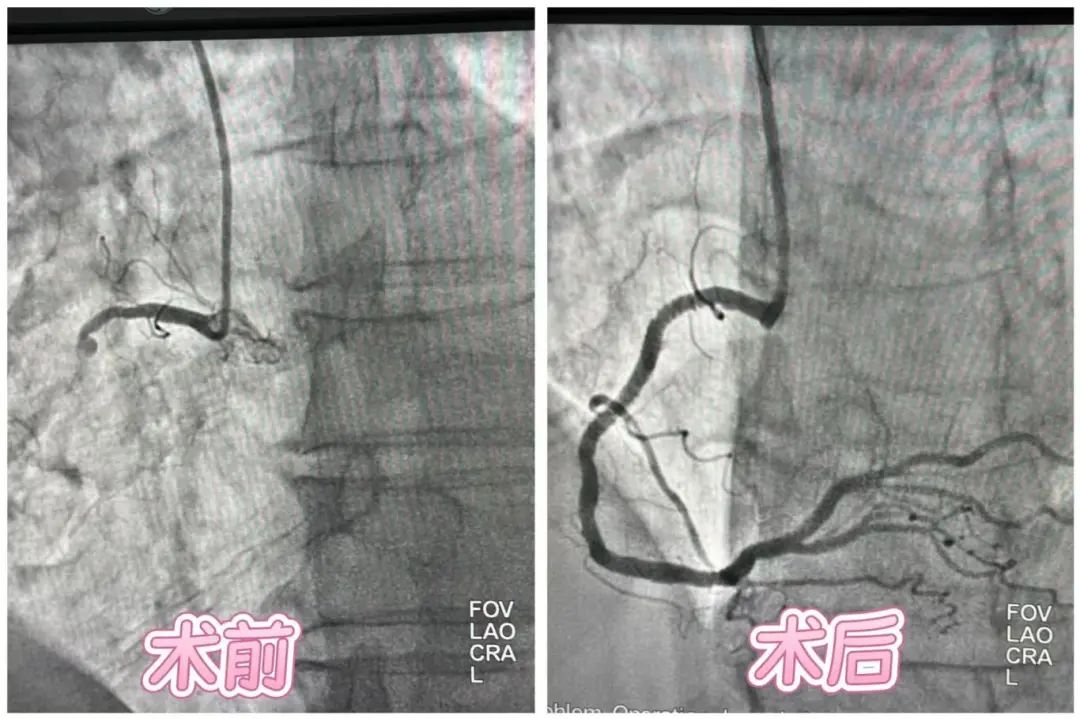

微创联合术式破局!脑病中心成功救治左下肢静脉闭塞患者